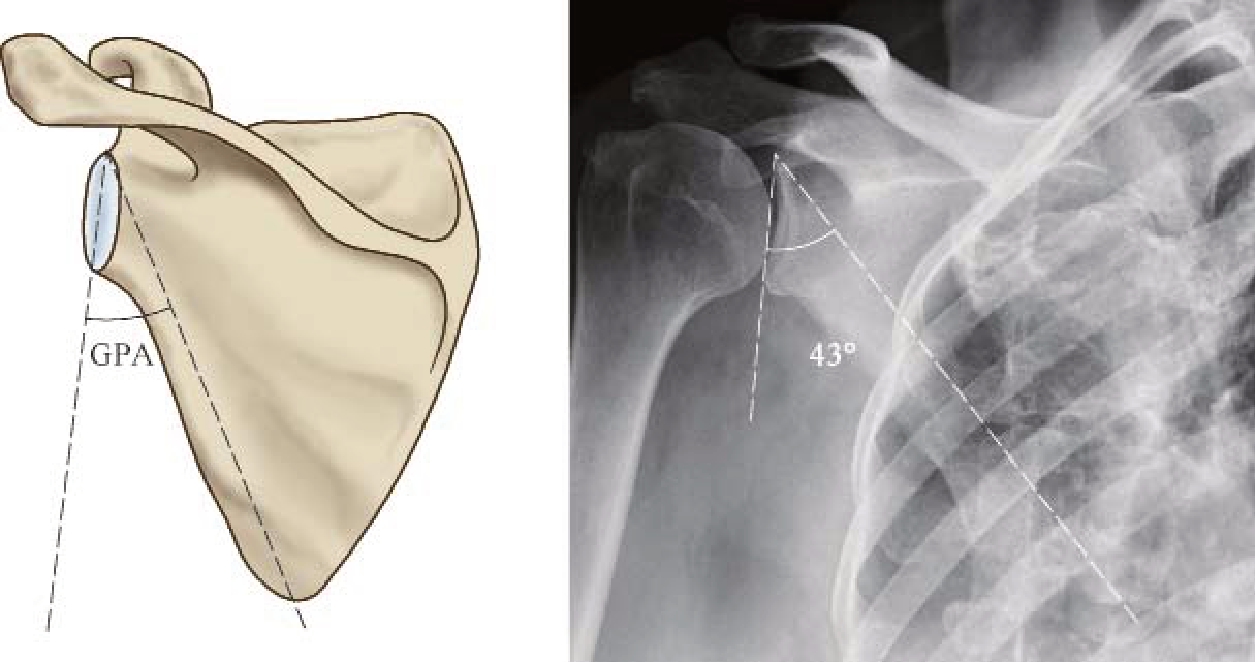

(1)盂极角:Bestard提出盂极角 (the glenopolar angle,GPA)的概念来描述肩胛盂和肩胛颈之间的关系[29]。盂极角测量:标记肩关节Grashey位上肩胛盂上下缘之间连线和肩胛盂上缘、肩胛骨下角顶点之间连线,测量二线之间夹角。盂极角的正常值为30°~45°(图2—6)。正常人群中盂极角个体差异较大,但是同一个体左右肩关节之间差异较小,因此建议测量对侧肩关节值以供参考[30]

图2—6 盂极角

影响测量GPA准确性的关键是相应解剖标记点的定位,拍片要求射线方向和肩胛骨平面垂直,表现为肩胛盂前后缘之间互相重叠。目前推荐的测量方法是肩关节Grashey位片或三维CT [31]

GPA的临床意义:① 是否需要手术治疗的参考指标之一,肩胛骨骨折后GPA<20°需要手术治疗[32]。② 作为评价治疗疗效的指标:伤时GPA<30°,保守治疗疗效欠佳,术后GPA恢复至接近正常(30°),患者肩关节功能改善较好[32,33]